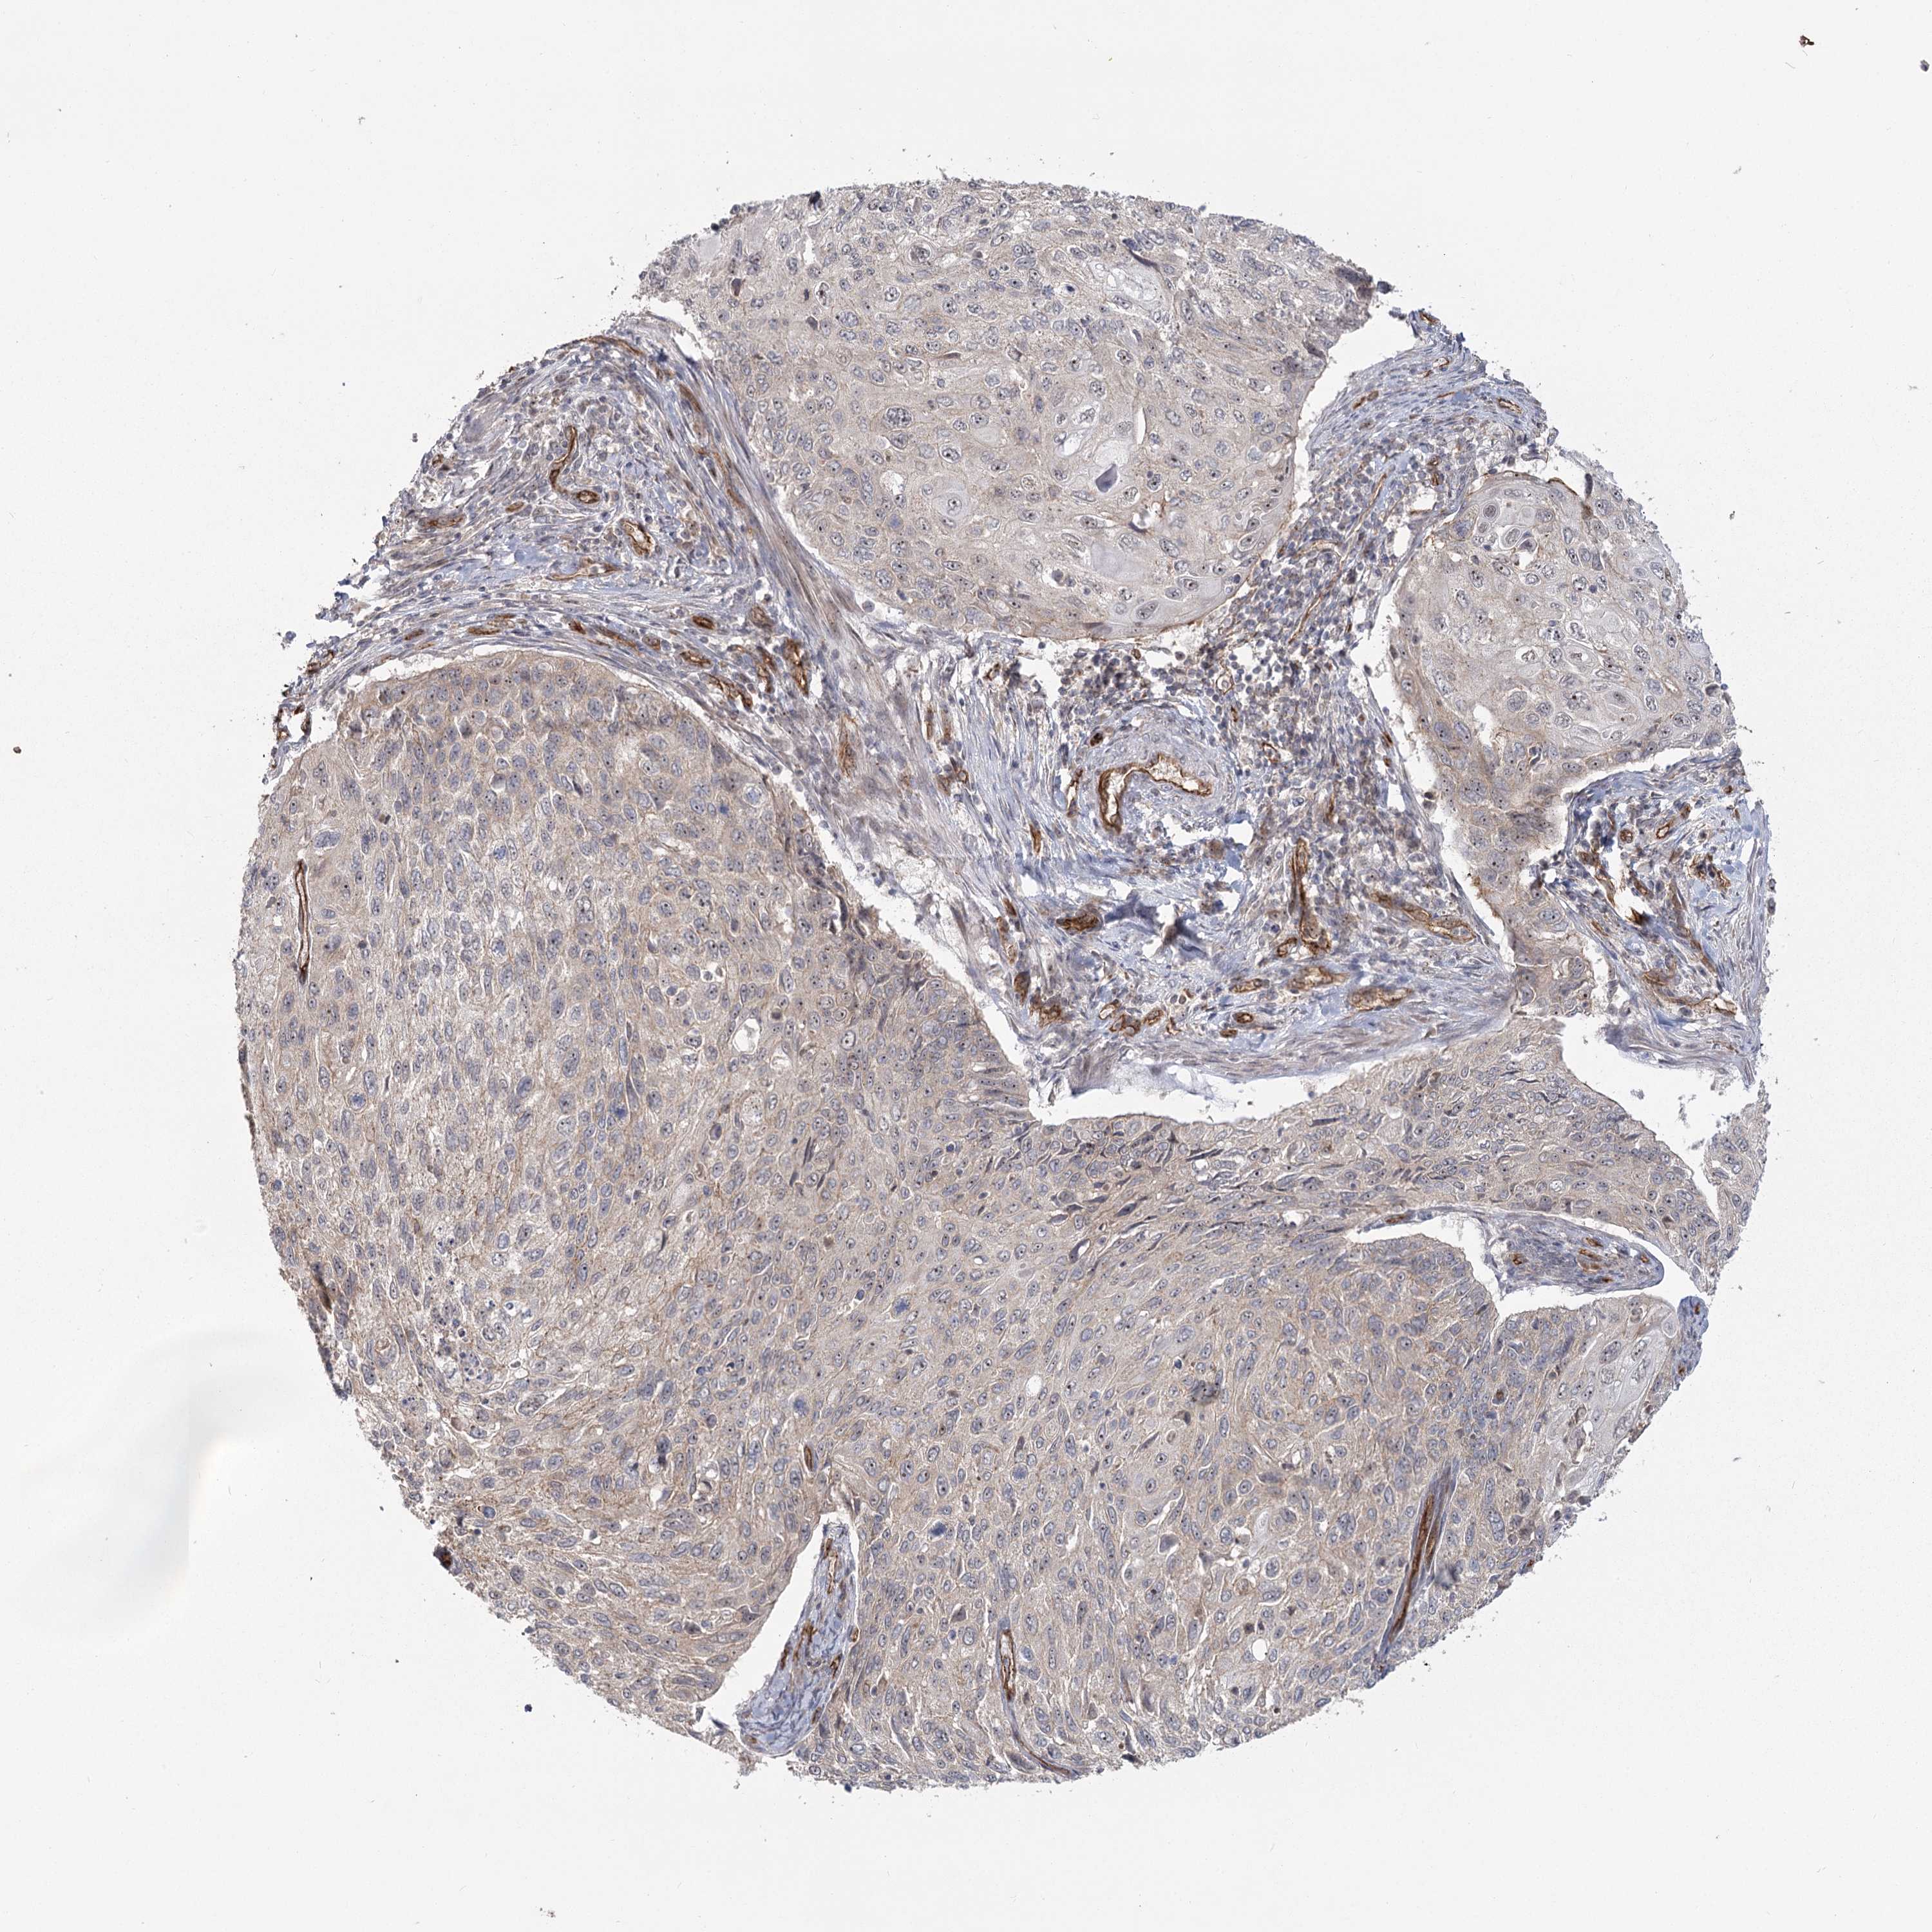

CERVICAL CANCER - Protein expressioni

A mouse-over function shows sample information and annotation data. Click on an image to view it in a full screen mode. Samples can be filtered based on level of antibody staining by selecting one or several of the following categories: high, medium, low and not detected. The assay and annotation is described here.

Note that samples used for immunohistochemistry by the Human Protein Atlas do not correspond to samples in the TCGA dataset.

Antibody stainingi

Antibody staining in the annotated cell types in the current human tissue is reported as not detected, low, medium, or high, based on conventional immunohistochemistry profiling in selected tissues. This score is based on the combination of the staining intensity and fraction of stained cells.

Each image is clickable and will lead to virtual microscopy that enables deeper exploration of all samples and also displays staining intensity scores, fraction scores and subcellular localization as well as patient and tissue information for each sample.

Antibody HPA036194

Staining

High

Medium

Low

Not detected

Intensity

Strong

Moderate

Weak

Negative

Quantity

>75%

75%-25%

<25%

None

Location

Nuclear

Cytoplasmic/membranous

Cytoplasmic/membranous,nuclear

Squamous cell carcinoma, NOS

Adenocarcinoma, NOS